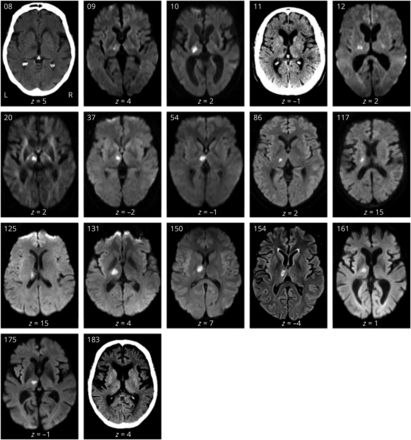

在报告回顾中确定的267例患者中,101例患者(64.1±14.6年;均值±标准差,女性40例,右撇子96例)符合纳入标准。左侧病变57例,右侧病变42例,双侧病变2例。从中风发作到记录相关中风症状的检查之间的平均时间为1.0天(SD 1.23;范围0-11天)。共有17名患者被发现有语言障碍(有关各自患者的详细缺陷描述和成像,请参见表1而且图1分别)。构音障碍48例,右侧运动障碍44例,左侧运动障碍32例,右侧感觉障碍34例,左侧感觉障碍37例。

(A)病变频率图:MRI叠加101例患者在MNI空间的病变重叠(ch2bet模板分布与MRIcron)。颜色条表示每个体素中病灶重叠的患者数量,热色表示该区域病变患者数量较多。最大病变重叠位于左腹侧核(MNI - 16, - 20,2;N = 24)。(B)在所有患者中,只有至少10% (n≥10)的受影响区域进行了基于体素的病变-症状映射分析。虚线标记丘脑边界。代表性轴向切片在MNI空间中,每个图像下方报告z坐标。蒙特利尔神经学研究所。